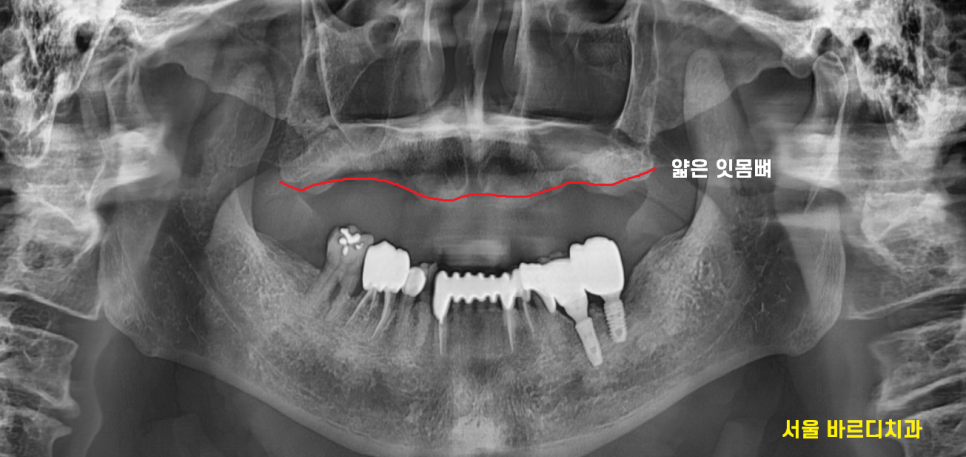

윗니의 경우 전체 치아 상실이 있네요

보험 틀니의 경우 7년에 한번씩 새로 보험 적용이 가능합니다.

오래 사용하시기도 하여

새롭게 제작하시는건 어떻냐 여쭤봤는데

문제는...

워낙 오래전부터 틀니를 사용하신터라

잇몸뼈가 얇아져있었습니다.

새롭게 제작한다고 하여도

금방 껄떡껄떡거리고

쉽게 빠질께 분명하였죠.